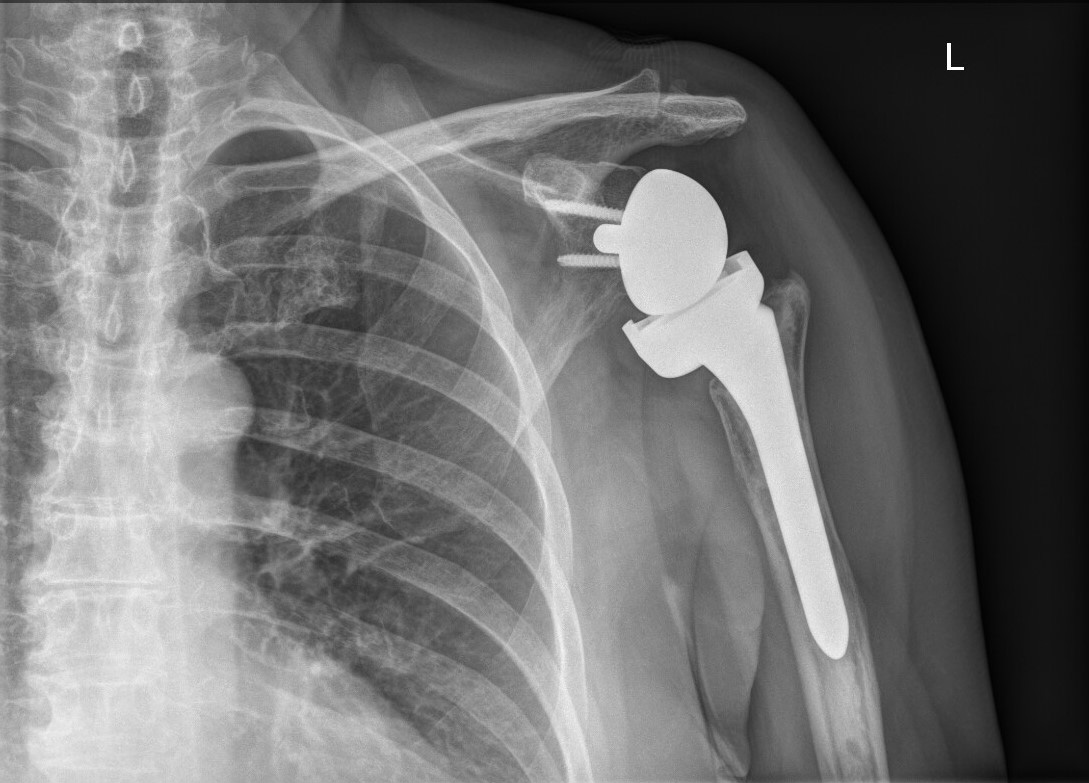

Už dvě desetiletí provádějí ortopedi Baťovy nemocnice náhrady ramenního kloubu a za tu dobu mají na svém kontě kolem čtyř set operací. V roce 2005 byli dokonce mezi prvními v České republice, kteří provedli totální náhradu ramenního kloubu nového typu. Výměna ramenních kloubů přitom v každé nemocnici zdaleka není samozřejmostí.

Celkový počet odoperovaných endoprotéz ramene za dvacet let odhaduje Pavel Pilař na čtyři stovky, což jsou počty srovnatelné jako u specializovaných ortopedických klinik.

Totální náhrada ramenního kloubu nejčastěji řeší artrózu ramenního kloubu, nejtěžší úrazové stavy i neuspokojivé poúrazové nálezy.